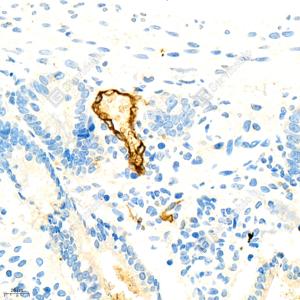

IHC检测MAdCAM1蛋白(货号 GB111006). 样品: 小鼠胰腺炎, 4%多聚甲醛 (货号G1101) 固定12-24小时. 抗原修复: 柠檬酸抗原修复液(干粉, pH 6.0) (G1201), 98℃, 20分钟. —抗: 1: 1700稀释, 4℃ 孵育过夜. 二抗: HRP标记山羊抗兔IgG (H+L) (货号GB23303), 1: 200稀释, 室温孵育1小时. |

IHC检测MAdCAM1蛋白(货号 GB111006). 样品: 小鼠小肠, 4%多聚甲醛 (货号G1101) 固定12-24小时. 抗原修复: 柠檬酸抗原修复液(干粉, pH 6.0) (G1201), 98℃, 20分钟. —抗: 1: 1700稀释, 4℃ 孵育过夜. 二抗: HRP标记山羊抗兔IgG (H+L) (货号GB23303), 1: 200稀释, 室温孵育1小时. |

IHC检测MAdCAM1蛋白(货号 GB111006). 样品: 小鼠小肠, 4%多聚甲醛 (货号G1101) 固定12-24小时. 抗原修复: 柠檬酸抗原修复液(干粉, pH 6.0) (G1201), 98℃, 20分钟. —抗: 1: 1800稀释, 4℃ 孵育过夜. 二抗: HRP标记山羊抗兔IgG (H+L) (货号GB23303), 1: 200稀释, 室温孵育1小时. |

IHC检测MAdCAM1蛋白(货号 GB111006). 样品: 大鼠结肠, 4%多聚甲醛 (货号G1101) 固定12-24小时. 抗原修复: 柠檬酸抗原修复液(干粉, pH 6.0) (G1201), 98℃, 20分钟. —抗: 1: 1800稀释, 4℃ 孵育过夜. 二抗: HRP标记山羊抗兔IgG (H+L) (货号GB23303), 1: 200稀释, 室温孵育1小时. |

IHC检测MAdCAM1蛋白(货号 GB111006). 样品: 大鼠结肠, 4%多聚甲醛 (货号G1101) 固定12-24小时. 抗原修复: 柠檬酸抗原修复液(干粉, pH 6.0) (G1201), 98℃, 20分钟. —抗: 1: 500稀释, 4℃ 孵育过夜. 二抗: HRP标记山羊抗兔IgG (H+L) (货号GB23303), 1: 200稀释, 室温孵育1小时. |

IHC检测MAdCAM1蛋白(货号 GB111006). 样品: 大鼠胰腺炎(LPS), 4%多聚甲醛 (货号G1101) 固定12-24小时. 抗原修复: 柠檬酸抗原修复液(干粉, pH 6.0) (G1201), 98℃, 20分钟. —抗: 1: 500稀释, 4℃ 孵育过夜. 二抗: HRP标记山羊抗兔IgG (H+L) (货号GB23303), 1: 200稀释, 室温孵育1小时. |

IHC检测MAdCAM1蛋白(货号 GB111006). 样品: 大鼠胰腺炎, 4%多聚甲醛 (货号G1101) 固定12-24小时. 抗原修复: 柠檬酸抗原修复液(干粉, pH 6.0) (G1201), 98℃, 20分钟. —抗: 1: 1700稀释, 4℃ 孵育过夜. 二抗: HRP标记山羊抗兔IgG (H+L) (货号GB23303), 1: 200稀释, 室温孵育1小时. |

IHC检测MAdCAM1蛋白(货号 GB111006). 样品: 大鼠胰腺炎, 4%多聚甲醛 (货号G1101) 固定12-24小时. 抗原修复: 柠檬酸抗原修复液(干粉, pH 6.0) (G1201), 98℃, 20分钟. —抗: 1: 1800稀释, 4℃ 孵育过夜. 二抗: HRP标记山羊抗兔IgG (H+L) (货号GB23303), 1: 200稀释, 室温孵育1小时. |